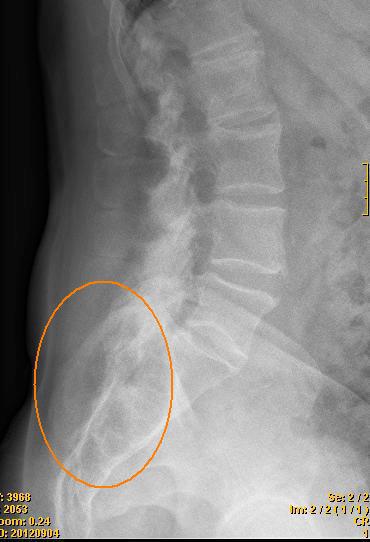

Quiste sacrocoxígeo

Quiste sacrocoxígeo, teratoma

El teratoma sacrococcígeo es el más común entre los tumores extragonadales de células germinales

en la infancia y la niñez temprana.